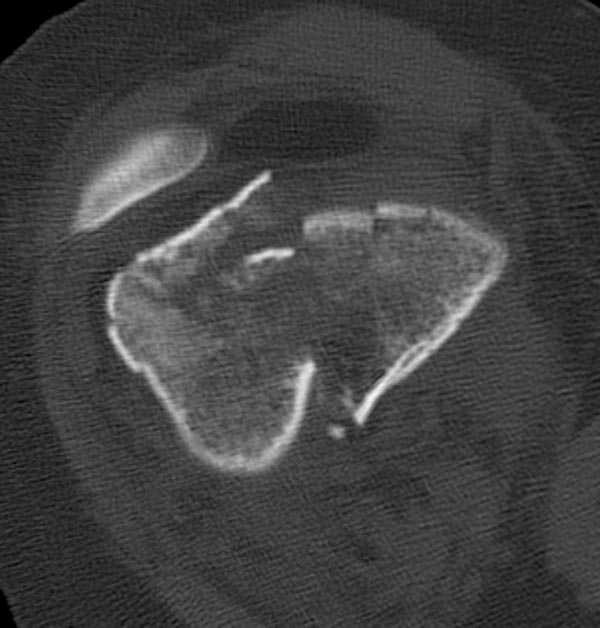

Бесспорно, предлагаемый ретроградный метод имеет свои преимущества, но имеется опасность при манипуляции интрамедуллярным гвоздем расколоть мыщелки.

Раскол можно предупредить шурупами, но короткий дистальный фрагмент навряд ли позволит добиться адекватной стабильности конструкции. Стандартные гвозди не рассчитаны для таких переломов, и если все таки желаете провести фиксацию гвоздем, тогда надо заказывать специальный custom made nail т.е. с расширенной возможностью дистальной блокировки.

Поэтому такие меж и над- мыщелковые переломы более предпочтительным считается фиксировать мыщелковыми пластинами